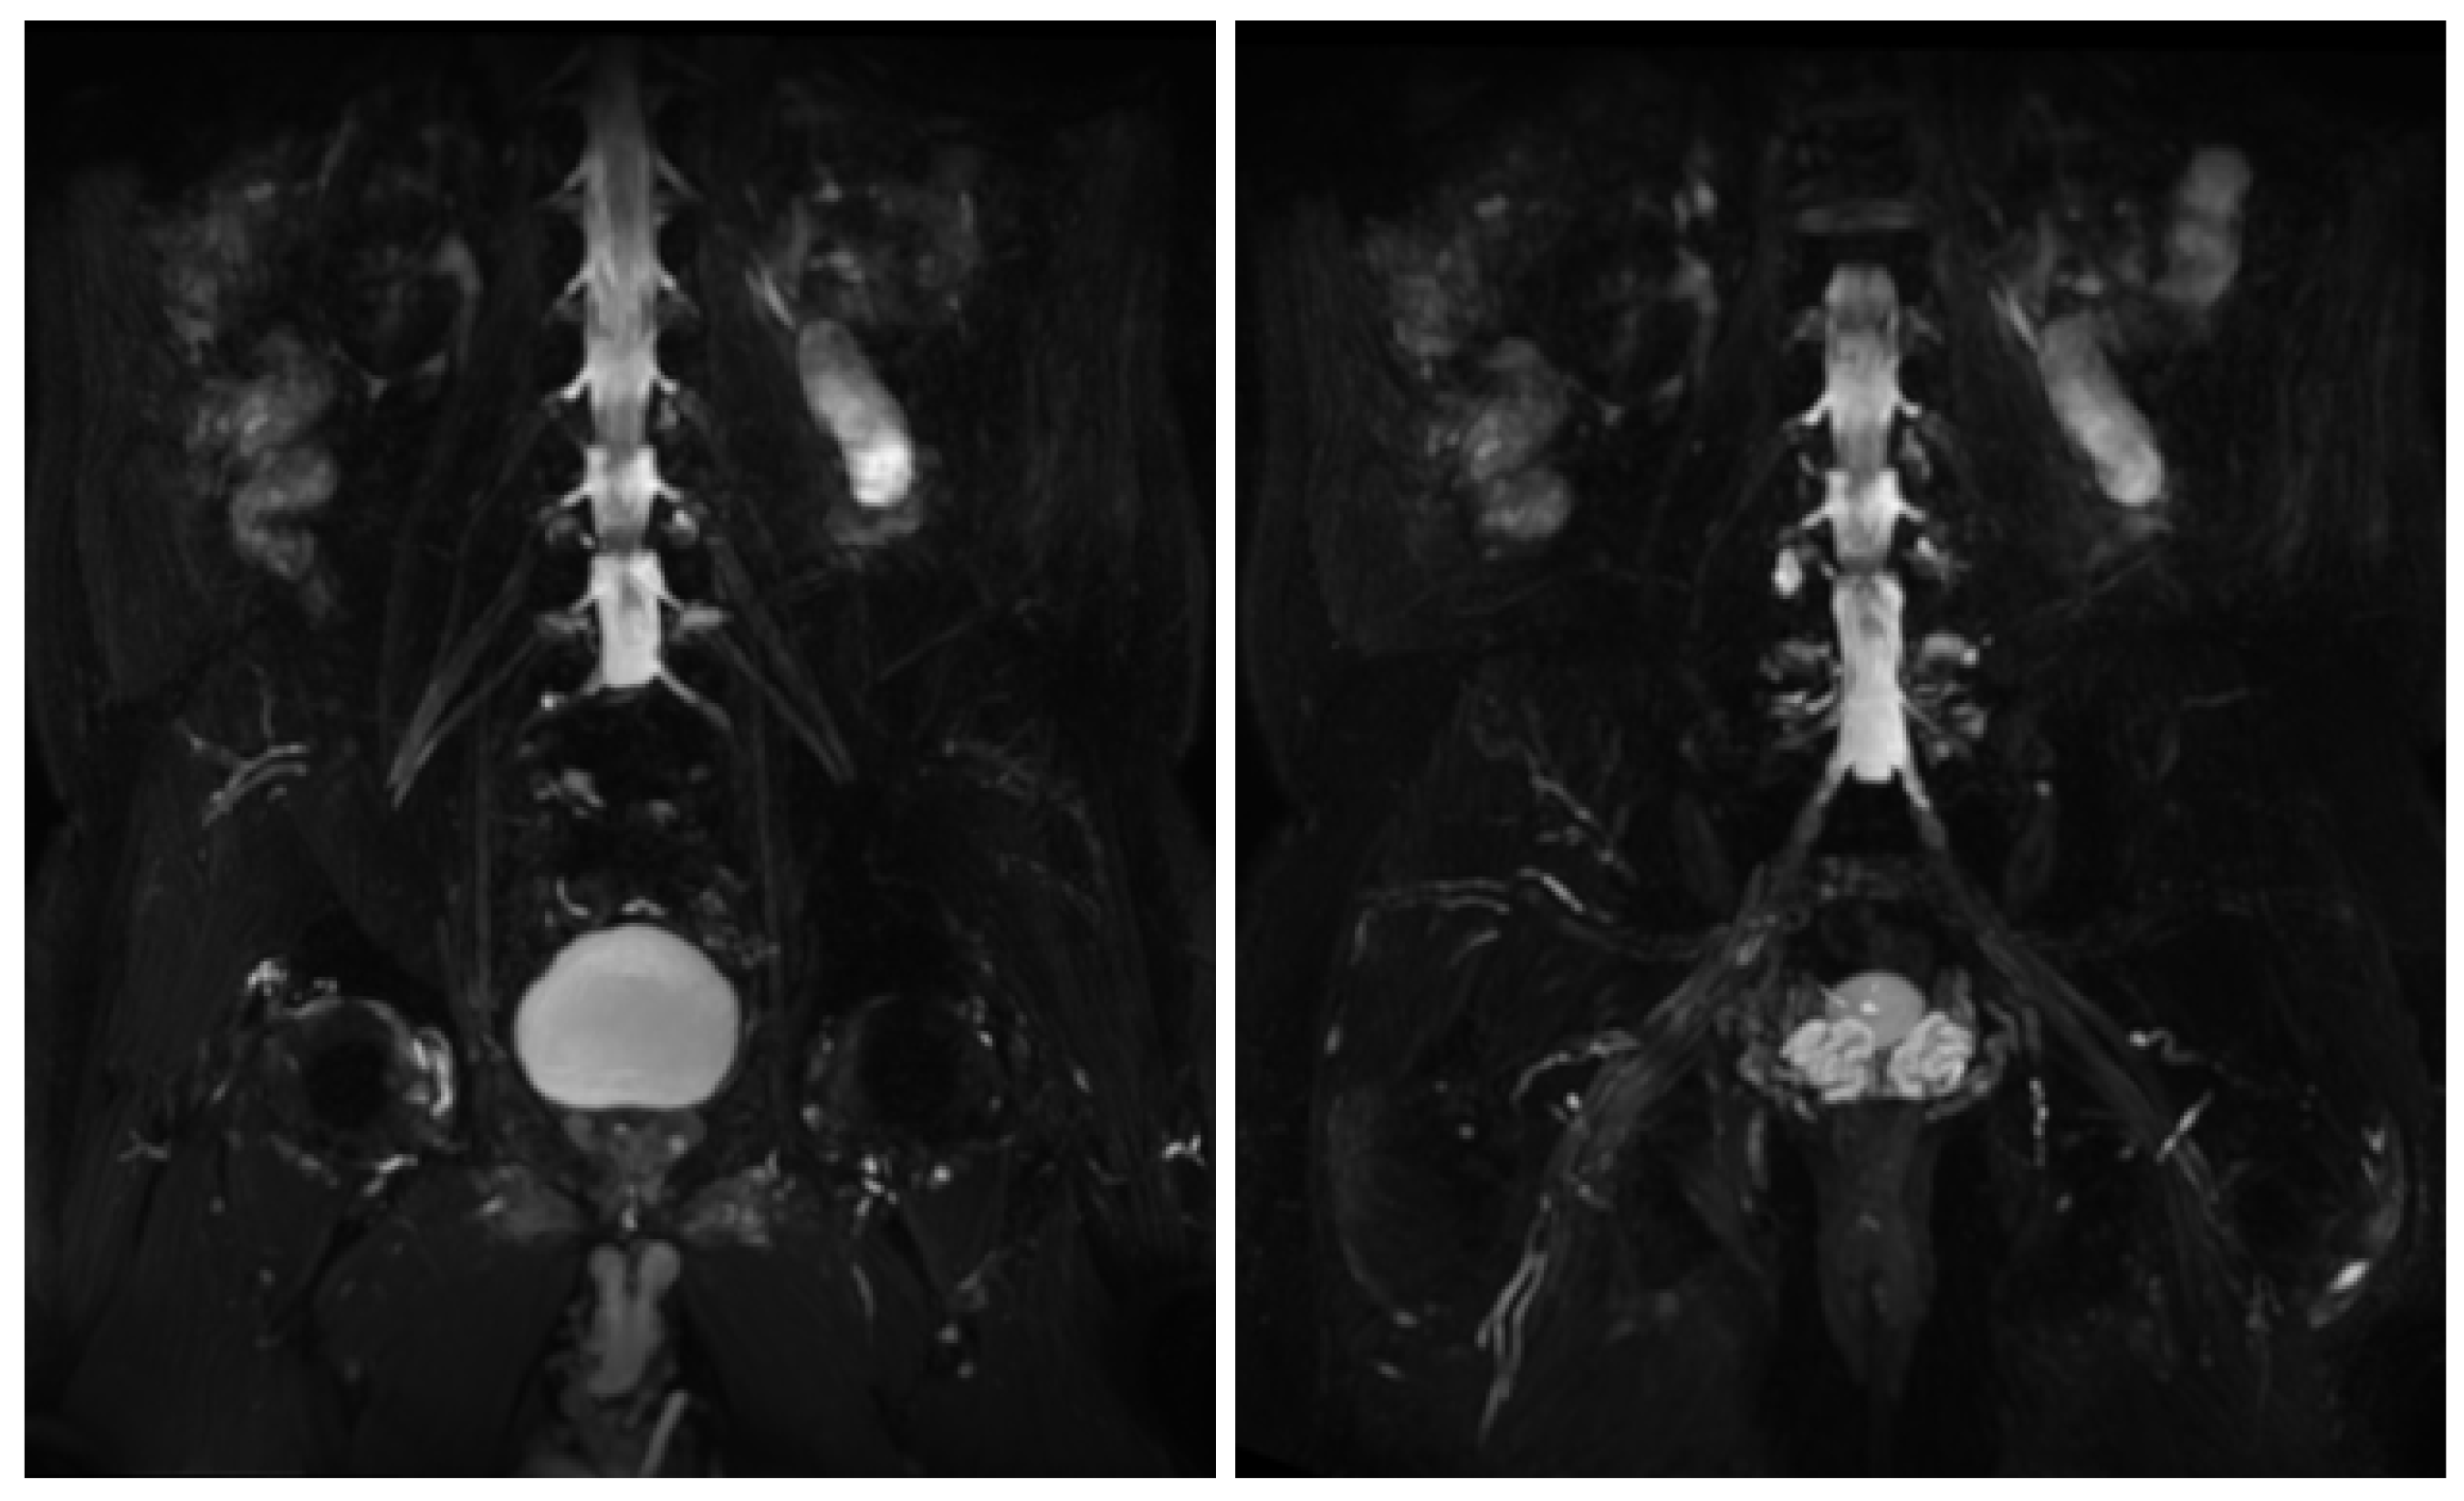

MR findings: brain and spinal MR were negative for pathological contrast enhancement of the roots of the cauda equina and radicles emerging from the spinal cord. Instead, swellings along the extracranial course of some V and VI cranial nerve branches had been reported (Figure 1). It was decided to integrate the study with MR neurography of the cranial nerves and the lumbosacral and brachial plexuses, which showed diffuse hypertrophy of the cranial nerves, and in particular of the oculomotor, trigeminal, facial, and hypoglossal (Figure 2) nerves with bilateral associations and asymmetric hypertrophy of the lumbosacral (Figure 3 and Figure 4) and brachialis (Figure 3 and Figure 5) plexuses.

Figure 1.

MR T2-weighted (top) and T1-weighted fat post-contrast contrast images (bottom). The images in (A) are in the coronal plane, those in (B) are in the sagittal plane and those in (C) are in the axial plane. The images show thickened and pathological cranial nerves with a cystic appearance, high signals in T2w images and almost no contrast enhancement. In both (A), yellow arrows indicate pathological V3 branches of the trigeminal nerve (transverse diameter after the foramen ovale: left 3.8 mm; right 10 mm); in both (B), yellow arrows indicate pathological facial nerve in the intraparotid course (transverse diameter in intraparotid course: left 6.7 mm vs. right 2.2 mm); in both (C), yellow arrows indicate pathological right V1 branch of the trigeminal nerve (transverse diameter after superior orbital foramen: right 6.9 mm vs. left 2.3 mm).